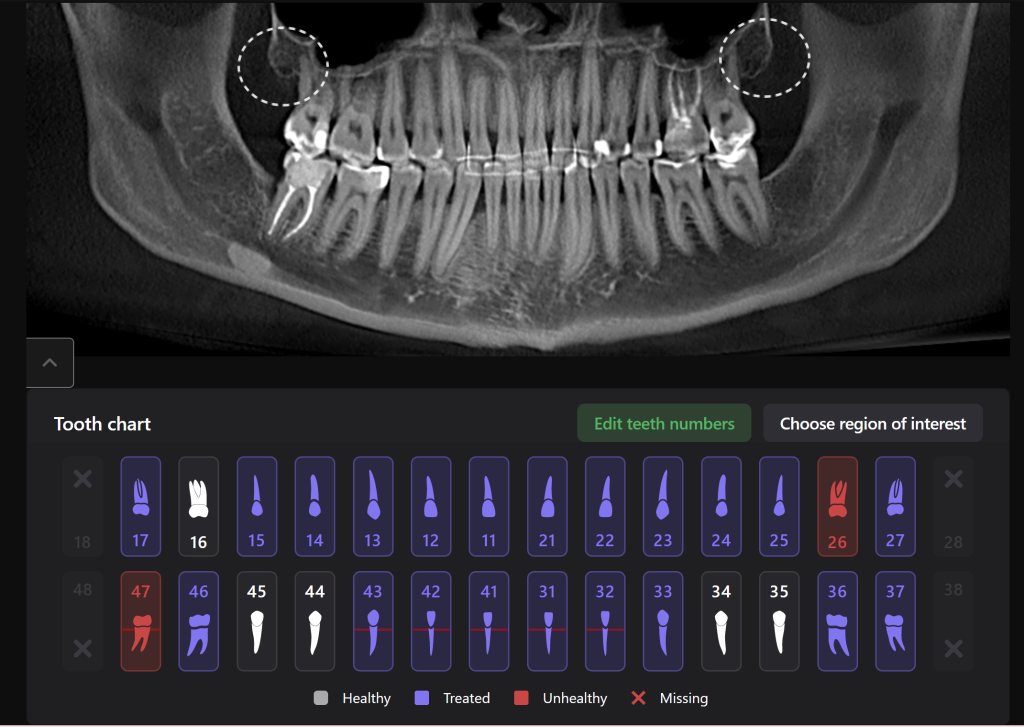

Extracting upper third molars can be difficult, if they are impacted and in contact with the maxillary sinus. Diagnocat AI will help you carefully plan your procedure, minimizing the risk of possible complications.

The “Third Molar Report” is a tool created by Diagnocat AI, it creates an optimal 3D visualization which helps to assess the position of the roots of the third molars relative to the roots of adjacent teeth and the floor of the maxillary sinus.

Teeth 18 (Universal 1) and 28 (Universal 16) were removed with minimal surgical trauma and without causing damage to the maxillary sinuses.